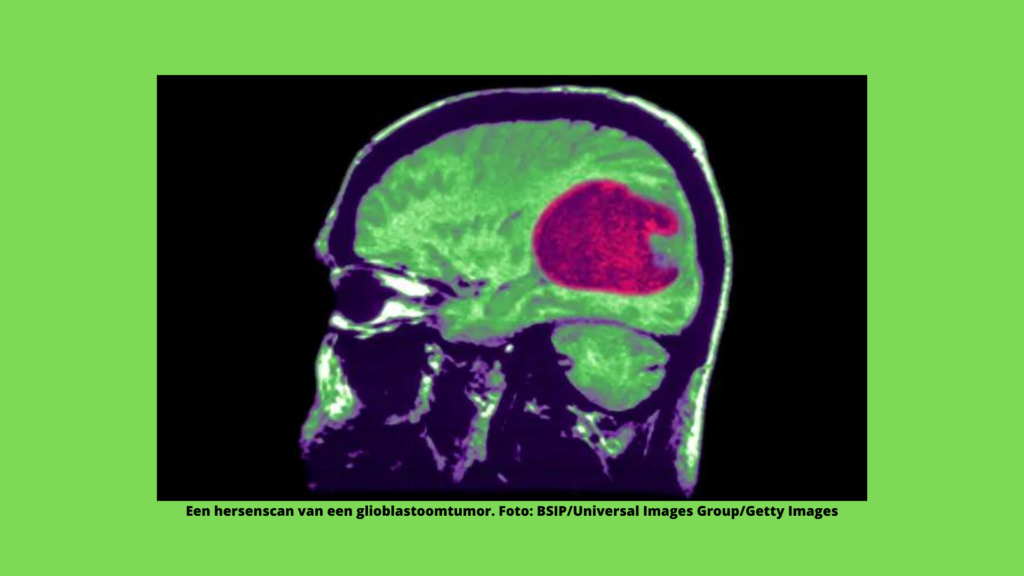

Baanbrekend NHS-onderzoek richt zich op hersentumoren vóór de operatie